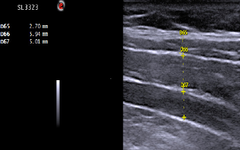

[Fig. 1] Ultrasonography-thickness of abdominalis (D65:external oblique abdominalis, D66:internal oblique abdominalis, D67:transvers abdominalis)